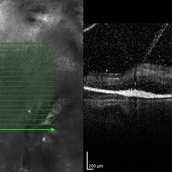

Behcet's Disease Behcet's DiseaseMar 13 2013 by Hamid Ahmadieh, MD OCT of the right eye of a 23-year-old man with retinal vasculitis and branch retinal vein occlusion (BRVO) due to Behcet's disease . Photographer: Solmaz Shahmohammad, Negah Eye Center, Tehran Imaging device: Topcon OCT Condition/keywords: branch retinal vein occlusion (BRVO), optical coherence tomography (OCT), retinal vasculitis